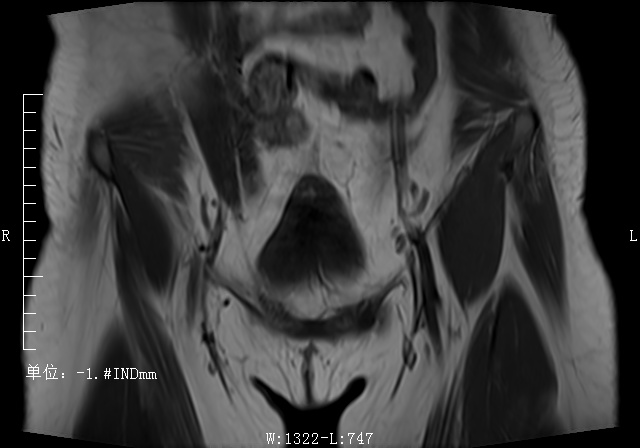

T2压脂矢状位

T2压脂矢状位 T1横轴位

T1横轴位 T2横轴位

T2横轴位 T1冠状位

T1冠状位 ADC

ADC T1压脂增强横轴位

T1压脂增强横轴位 T1压脂增强冠状位

T1压脂增强冠状位 T1压脂增强矢状位

T1压脂增强矢状位病案讨论

影像表现:子宫右后方见卵圆形软组织肿块影,与子宫后缘密切相连,病灶边缘清晰,病灶呈T1低信号T2低信号为主,其内夹杂少许散在斑片状T2高信号区,增强扫描病灶呈明显强化,与子宫肌层强化类似。盆腔未见明显肿大淋巴结,盆腔见片状压脂明显高信号影。

影像诊断:子宫浆膜下肌瘤。

MRI表现: 是发现和诊断子宫肌瘤最敏感的方法。在T1WI上,子宫肌瘤的信号强度类似子宫肌;然而在T2WI上,典型肌瘤呈明显低信号,边界清楚,与周围子宫肌信号形成鲜明对比。本例病灶与子宫后缘关系密切,病灶边缘清晰,T2呈较低信号,且增强呈明显强化,均符合较典型子宫肌瘤。